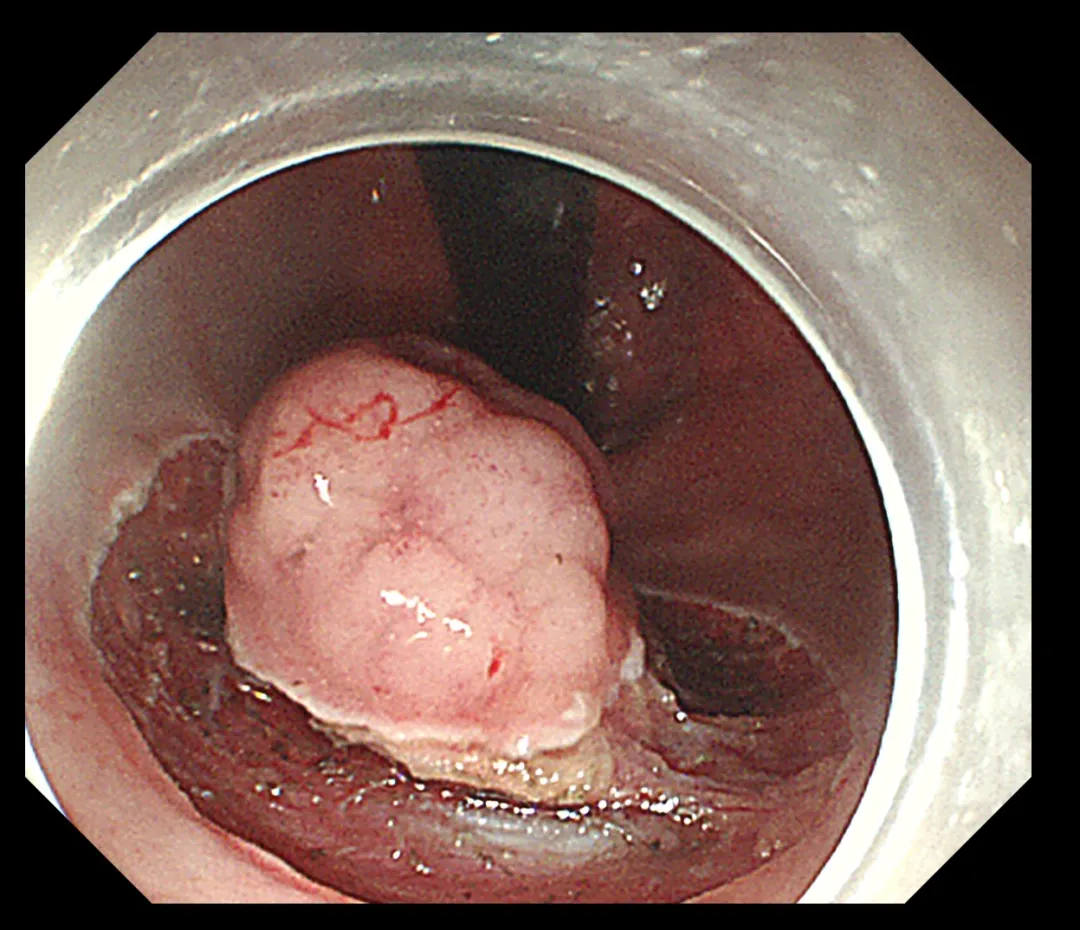

术中影像

手术过程中,内镜团队凭借精湛的技艺与细腻的操作,在方寸之间的肠腔内进行了“精雕细琢”。他们巧妙运用肠镜下黏膜剥离技术(ESD),将肿物从黏膜层完整剥离,既彻底根治了病变,又最大限度地保护了肛门的正常结构与功能。这一成果的实现,无疑为患者术后生活质量的提升奠定了坚实基础。术后,患者恢复状况良好,未出现任何并发症,现已顺利康复出院。